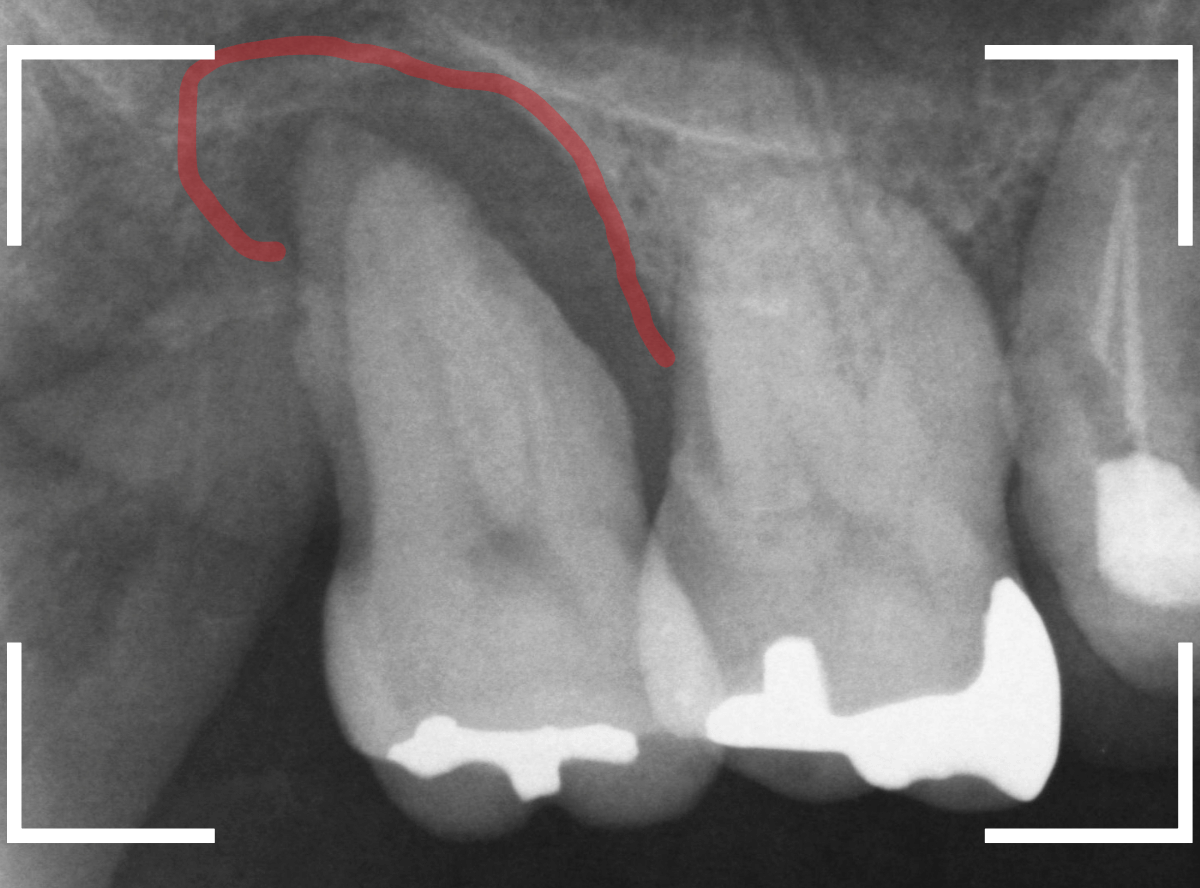

レントゲン写真で状況を確認します。

赤い線が歯周病で骨が失われたラインです。

歯の周囲全体の骨が大きく失われているのがわかります。

つまり、歯をささえる周囲の骨がほとんどなく、歯肉の中に埋まっているだけ、といった状況です。

これでは、噛むたびに痛くても仕方ありませんし、また、治療で骨が回復するのも見込めません。

それどこか、手前の歯にも歯周病が進行してしまうかもしれません。

残念ながら、抜歯が必要な旨をご説明し、行う事になりました。

周囲の骨が失われてグラグラの歯ですから、抜歯はあっという間に終わりました。